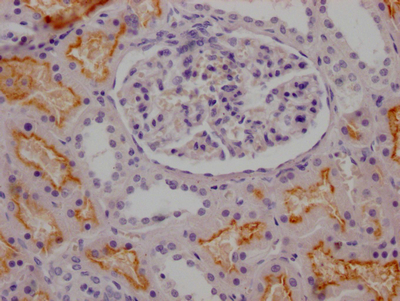

IHC image of CSB-RA268157A0HU diluted at 1:100 and staining in paraffin-embedded human kidney tissue performed on a Leica BondTM system. After dewaxing and hydration, antigen retrieval was mediated by high pressure in a citrate buffer (pH 6.0). Section was blocked with 10% normal goat serum 30min at RT. Then primary antibody (1% BSA) was incubated at 4℃ overnight. The primary is detected by a Goat anti-rabbit IgG polymer labeled by HRP and visualized using 0.05% DAB.